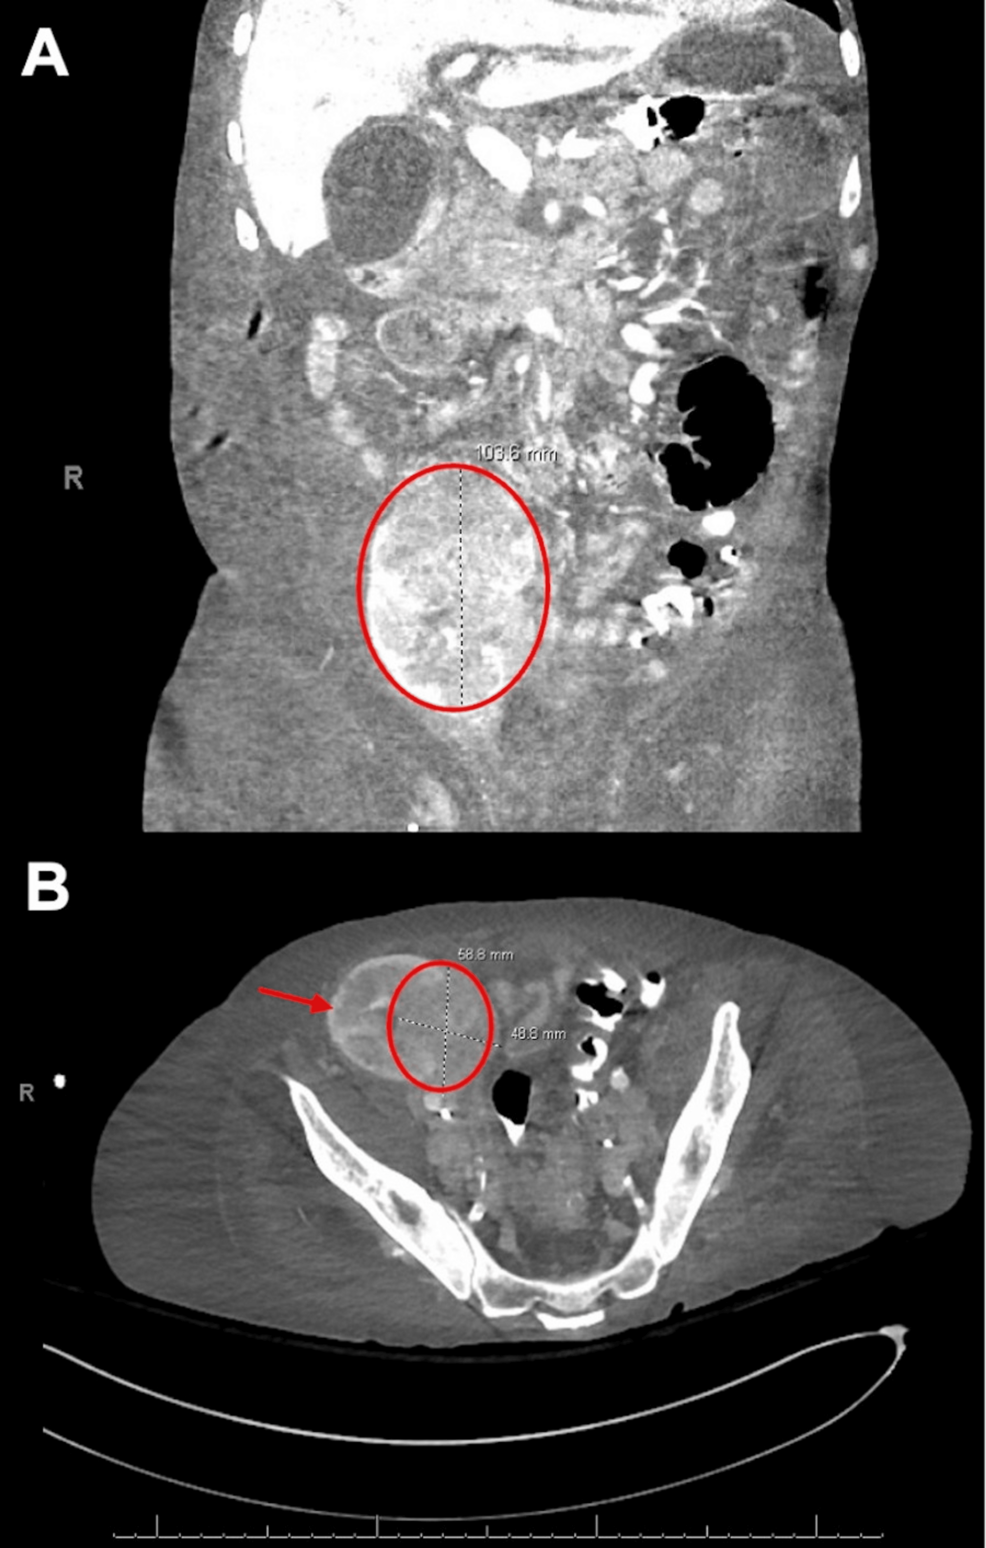

Home Kidney TransplantationCureusKaposi Sarcoma in an Allograft Kidney Presenting as Acute Kidney Injury With No Cutaneous Lesions: A Case ReportKaposi sarcoma (KS) is an angioproliferative neoplasm linked to human herpesvirus-8 (HHV-8) and occurs more frequently in immunosuppressed….1 day ago

CureusKaposi Sarcoma in an Allograft Kidney Presenting as Acute Kidney Injury With No Cutaneous Lesions: A Case ReportKaposi sarcoma (KS) is an angioproliferative neoplasm linked to human herpesvirus-8 (HHV-8) and occurs more frequently in immunosuppressed….1 day ago